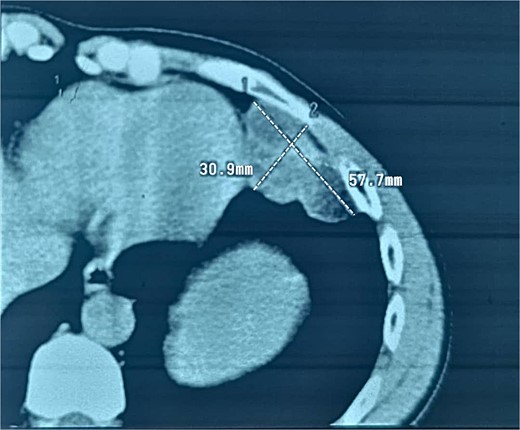

A 38-year-old male educator and part-time farmer with no notable cancer history in his family and a non-smoking background sought medical attention. His medical records included a left inguinal hernia repair two years prior and an ischemic stroke six years ago, for which he was undergoing ongoing treatment with clopidogrel, aspirin, and rosuvastatin. The patient reported swelling in the right inguinal region, without any other symptoms. The patient was prepared for surgery to repair the hernia. Upon opening the hernial sac, a thickened wall was observed. Aspiration was conducted to exclude bladder involvement, yielding cloudy, serous fluid indicative of ascites and omental thickening. Based on these observations, samples from the hernial sac wall (peritoneum), omentum, and ascitic fluid were submitted for histopathological analysis, and the hernia was repaired (Fig. 1). Peritoneal surgical biopsy showed that the peritoneal tissue fragments involved epithelioid cell malignant neoplasms with tubular and papillary formations and stromal infiltration. An IHC study revealed Calretinin and CK5/6 markers (mesothelial cell markers) were diffusely positive in the tumor, leading to a diagnosis of malignant mesothelioma. (Fig. 2 and 3) CEA levels were assessed and found to be within the normal limits. Contrast-enhanced computed tomography (CT) of the chest, abdomen, and pelvis revealed a 58 × 31 mm lobulated mass with multiple septate cavities in the lateral and basal pleura of the left lower lobe (Figs 4–6). The scan also showed thickening of the omentum, mesentery, and peritoneum, consistent with a left pleural mesothelioma with peritoneal and omental metastases. Oncologists diagnosed the patient with stage 4 pleural mesothelioma. The patient was determined to require oncological treatment consisting of eight cycles of cisplatin combined with gemcitabine. Unfortunately, the patient died during the fourth chemotherapy cycle.